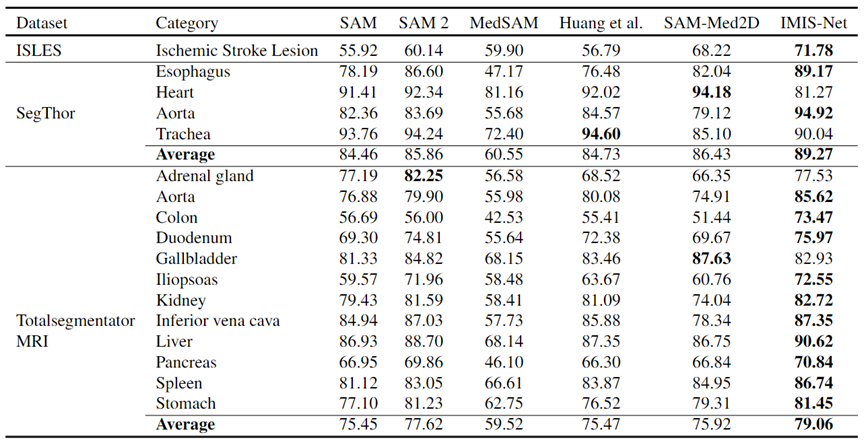

03 Zero-shot性能

图6. 在三个外部数据集上的Zero-shot性能

IMIS-Bench 提供了一个统一的基准框架,对 IMIS-Net 和现有交互式分割方法进行了全面、系统的性能评估。实验表明,IMIS-Net 在多种模态和任务场景下显著超越现有技术。同时,团队还对多种交互策略对分割性能的影响进行了深入研究,为模型的优化和交互设计提供了宝贵的指导。

本研究提出了IMed-361M,一个专注于交互式医学图像分割的基准数据集。该数据集包含了各种模态的大量医学图像、广泛的分割场景以及密集的掩码,超越了现有仅限于单一任务或简单集成的数据集。利用该数据资源,团队开发了通用的交互式医学图像分割基线模型IMIS-Net,使用户能够通过交互方式(包括点击、边界框、文本提示及其组合)生成符合临床需求的分割结果。与现有基础模型的对比实验结果表明,IMIS-Net在性能上具有显著优势,并在未见过的场景中展现出较强的可迁移性。值得注意的是,IMIS-Net通常需要更少的交互即可达到相当的性能,提高了其在实际应用中的实用性。